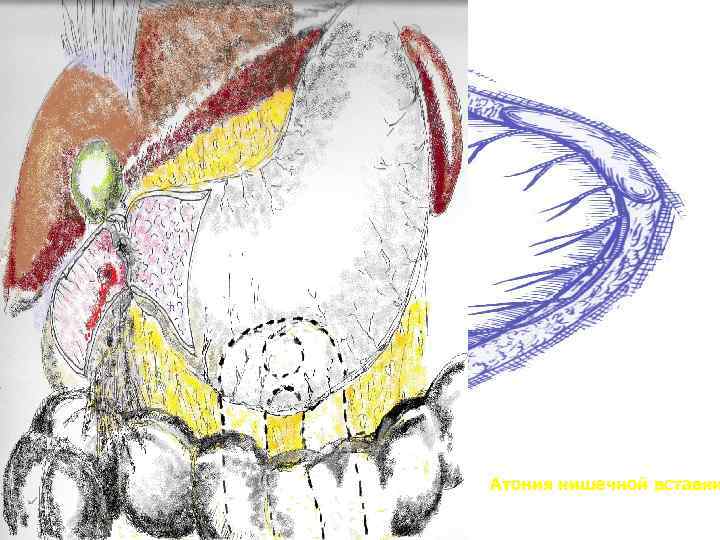

Реконструктивная гастроеюнопластика при демпинг синдроме после резекции желудка по второму способу Бильрота

Атония кишечной вставки